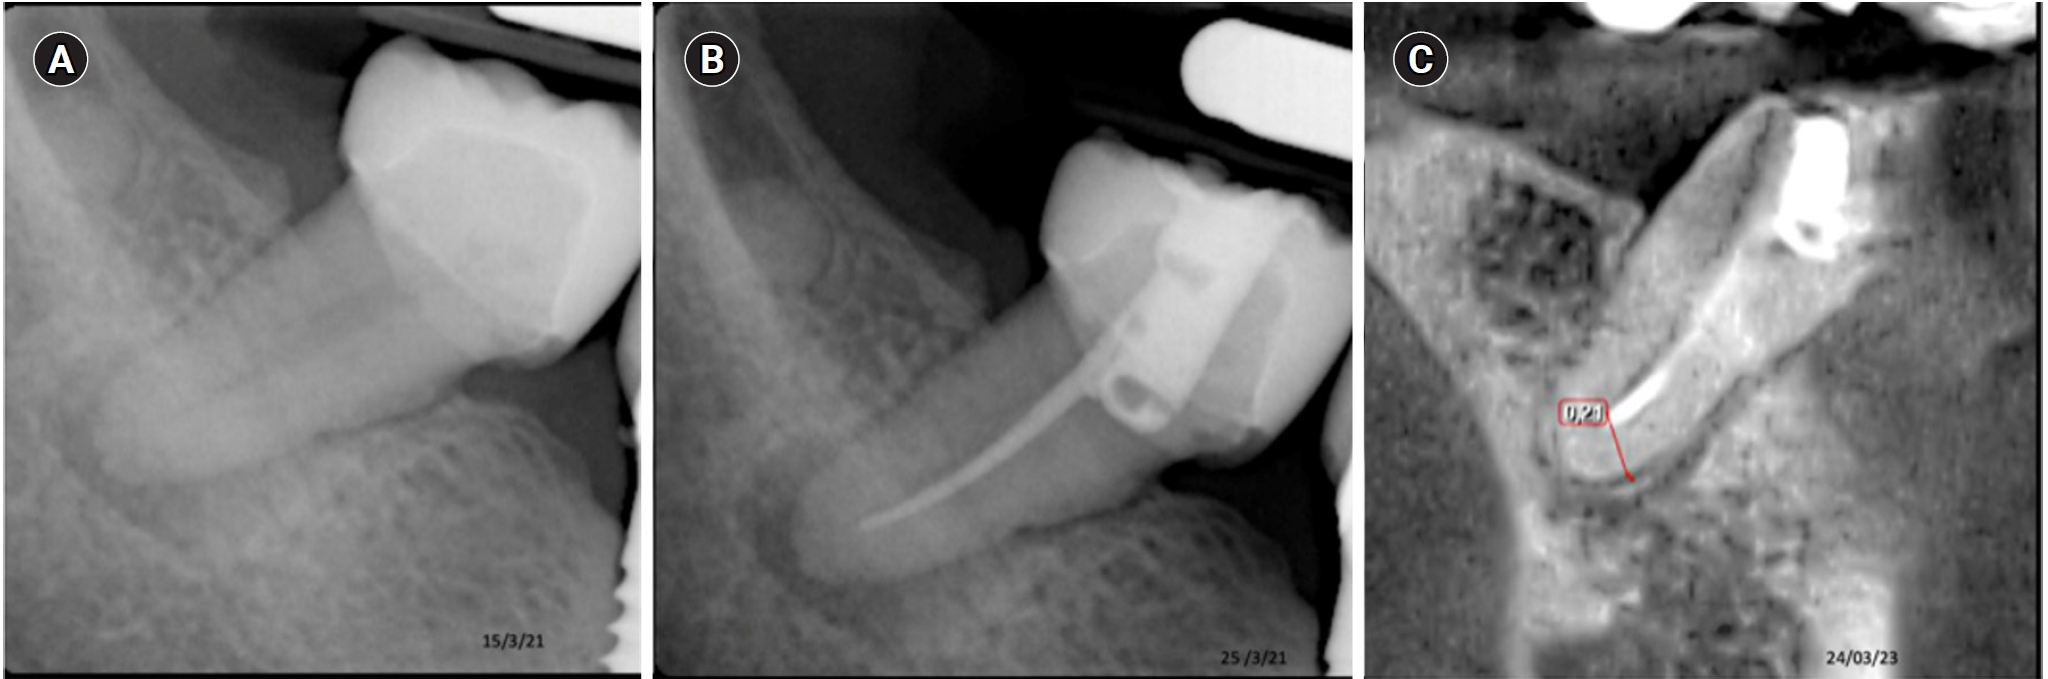

This image shows tooth 37 diagnosed with pulp necrosis with a chronic periapical abscess. (A) Diagnostic X-ray. (B) Immediate after obturation. (C) Tomographic control where complete healing is evident after 45 months.

This image shows tooth 27 diagnosed with pulp necrosis and asymptomatic apical periodontitis. (A) Diagnostic X-ray. (B) Immediate after obturation. (C) Tomographic control where an apical image in the process of healing is observed after 24 months.

Tooth 36 with a diagnosis of Pulp necrosis with acute periapical abscess. (A) Diagnostic X-ray. (B) Immediate after obturation. (C) Tomographic control after 24 months. showing the apical lesion in the same manner as in the initial X-ray, considered a failure.